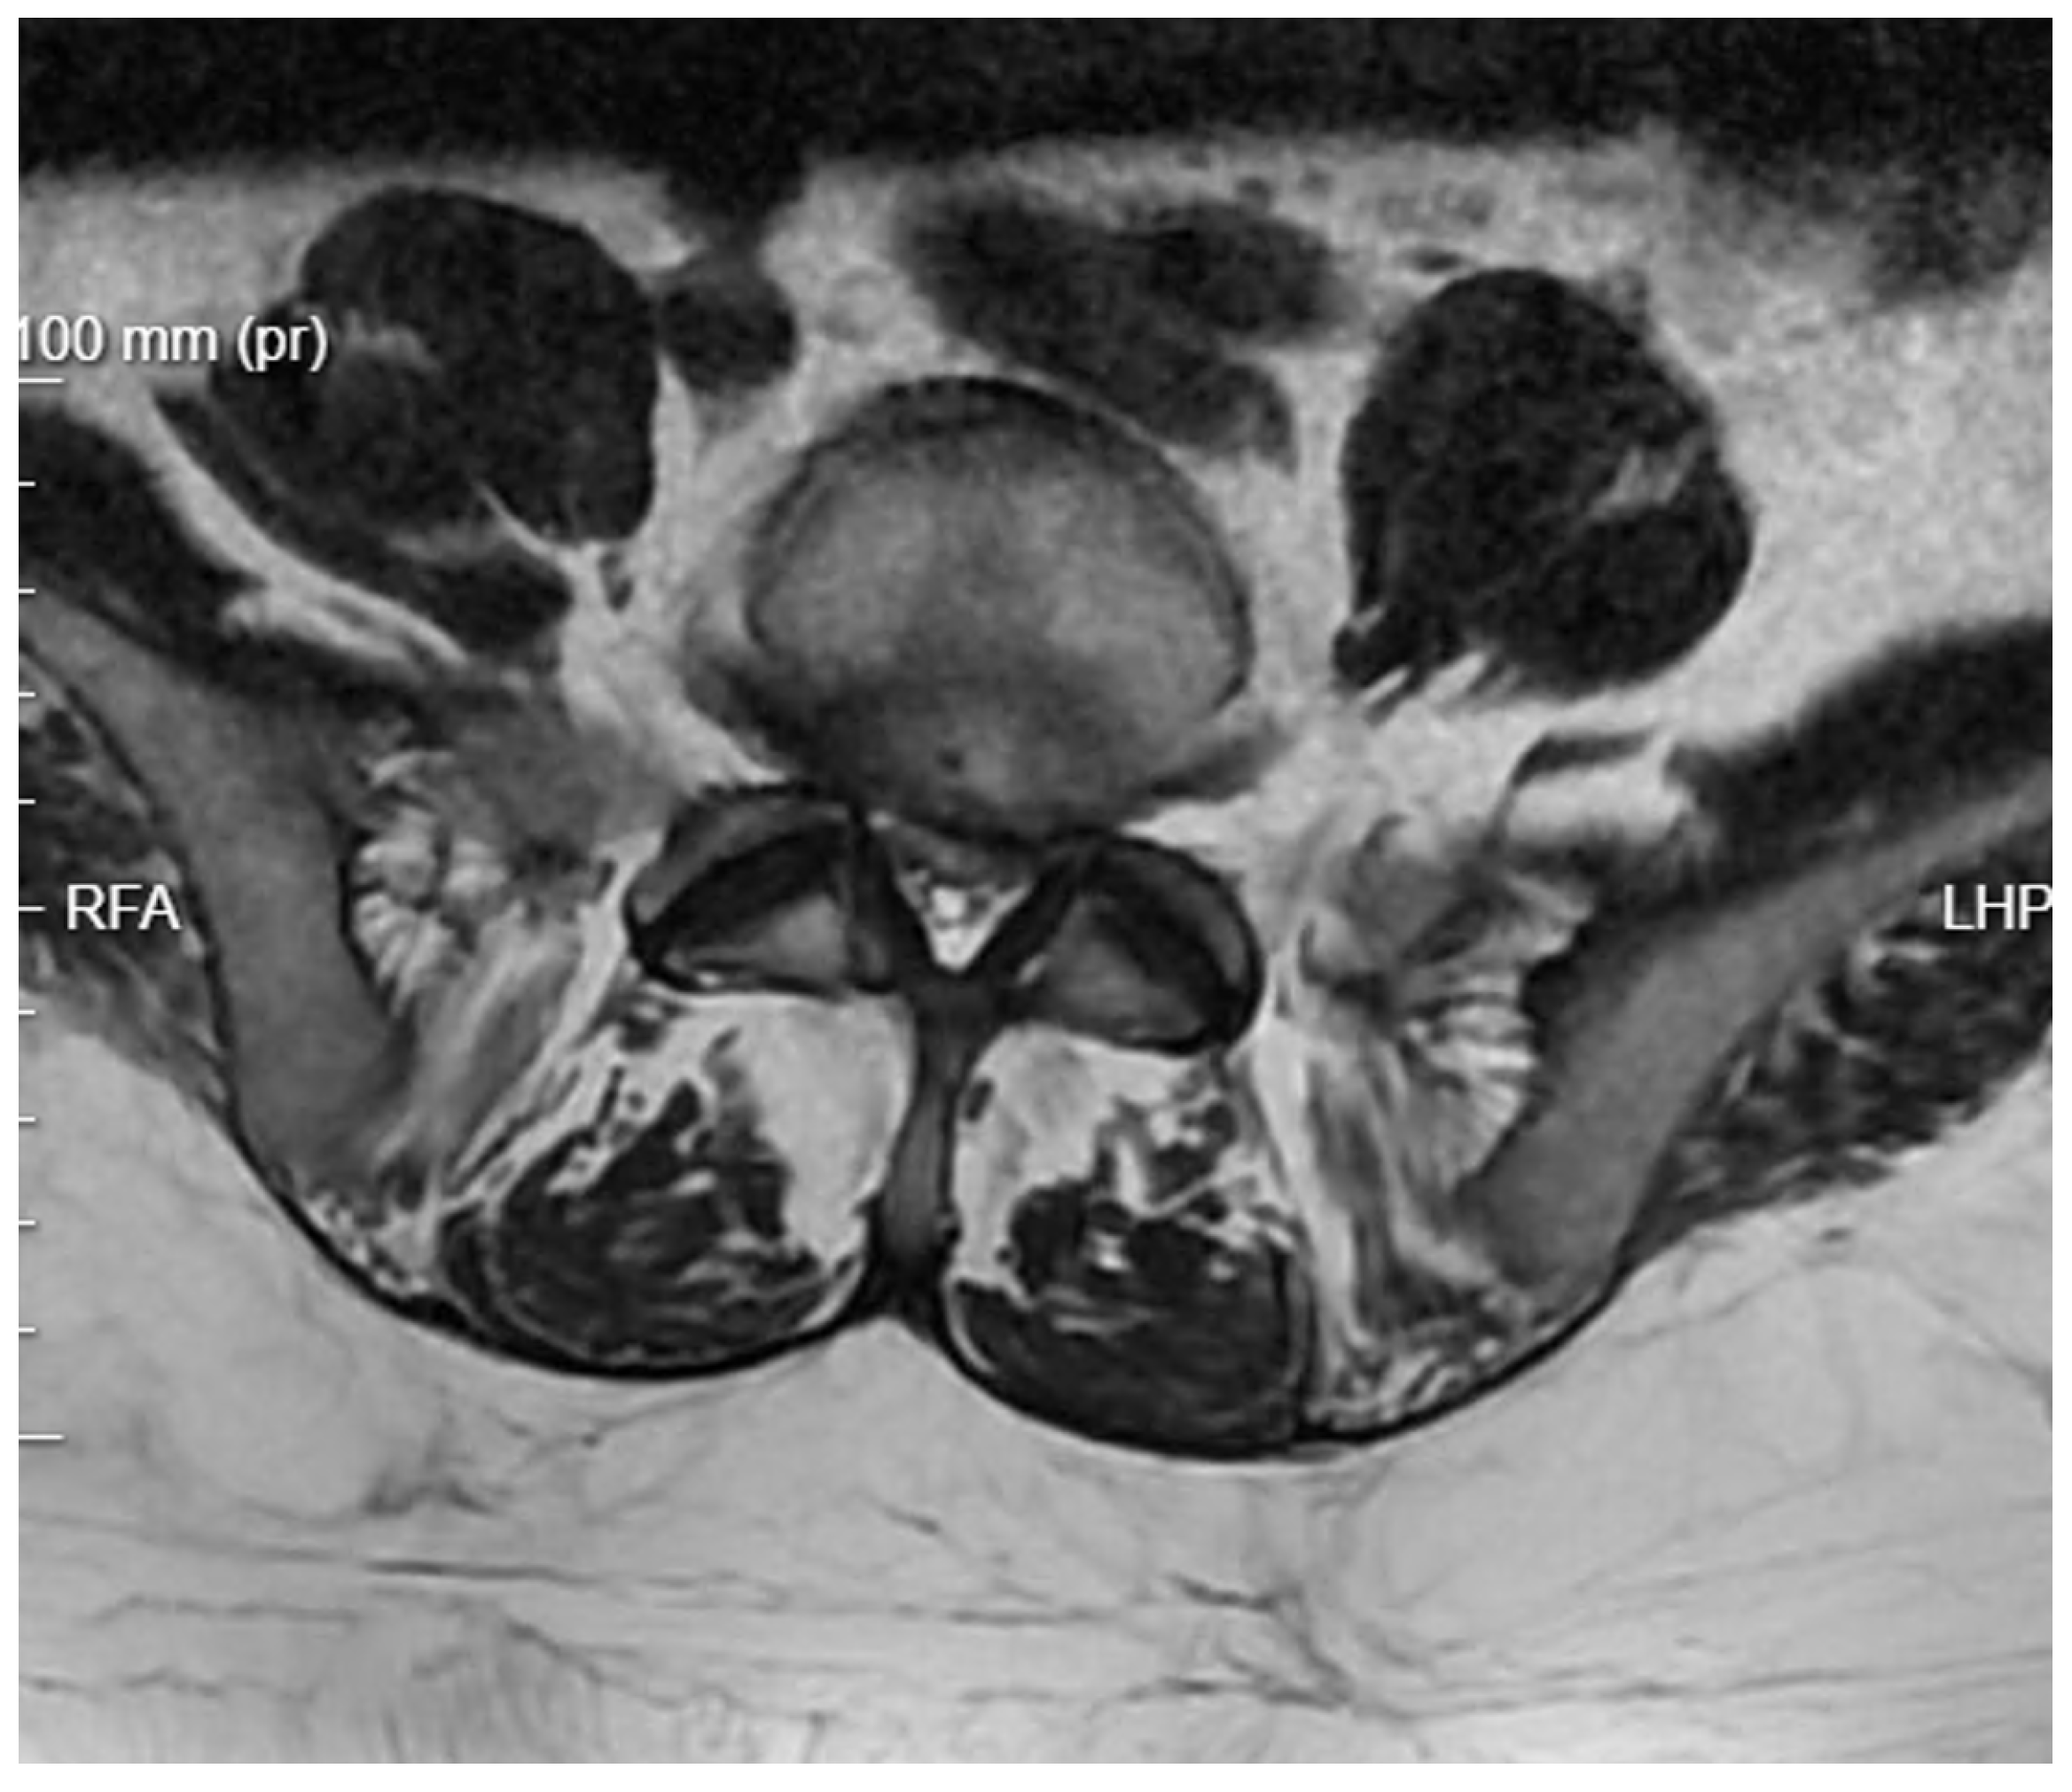

Further Intervention: Another MRI confirmed that despite extensive decompression, significant narrowing persisted at the operated level, with a markedly increased T2 signal in the disc space (Figure 7). A subsequent endoscopic transforaminal approach was employed. Inflammatory disc material and granulation tissue from the spinal canal were removed. Post-operative MRI showed a satisfactory degree of decompression of the canal. The patient was mobilized and transferred to the nephrology department due to further deterioration of renal function.

Figure 7. T2 axial MRI image at the L4/L5 level following previous open surgical treatment.